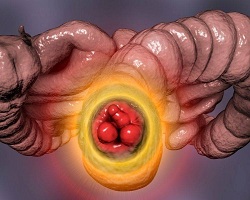

| Хемороиди или фиброваскуларни јастучићи аналног канала су део нормалне анатомске структуре и сматра се да су веома битни за одржавање континенције. Постоје два типа хемороида у односу на локализацију: спољашњи (у доњем делу аналног канала, испод зупчасте линије) и унутрашњи (у горњем делу аналног канала, изнад зупчасте линије). |

Апендицитис је упала слепог црева (апендикса). Слепо црево је узани део црева у облику црвуљка, дужине неколико центиметара. Једним крајем слепо црево везано је за почетни део дебелог црева, а други крај му се слепо завршава |